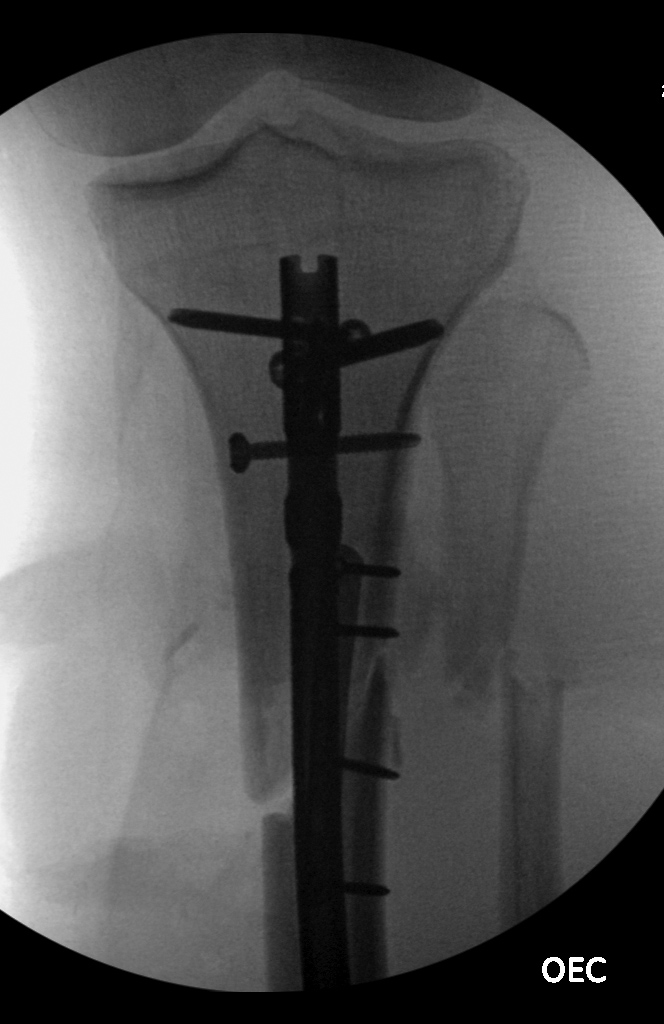

| Failure of fracture fixation due to ambulating against advice |

| Male patient with proximal tibia and fibula fractures treated by intramedullary nail and supplemental one-third tubular plate. Initial intraoperative fluoroscopic AP and lateral images (left two images) show the plate (arrow on lateral image). The patient ambulated against advice and was lost to follow-up. Two months later he again presented (right two images) to the clinic. There is now tibia fracture migration, and the proximal medial to lateral interlocking screw has backed out (AP view). The lateral view demonstrates fracture displacement with flexion deformity. The nail has troughed outside the proximal anterior tibia and is sitting within the soft tissues. The supplementary plate is broken, there is a broken interlocking screw, and abundant fracture callus is present. |